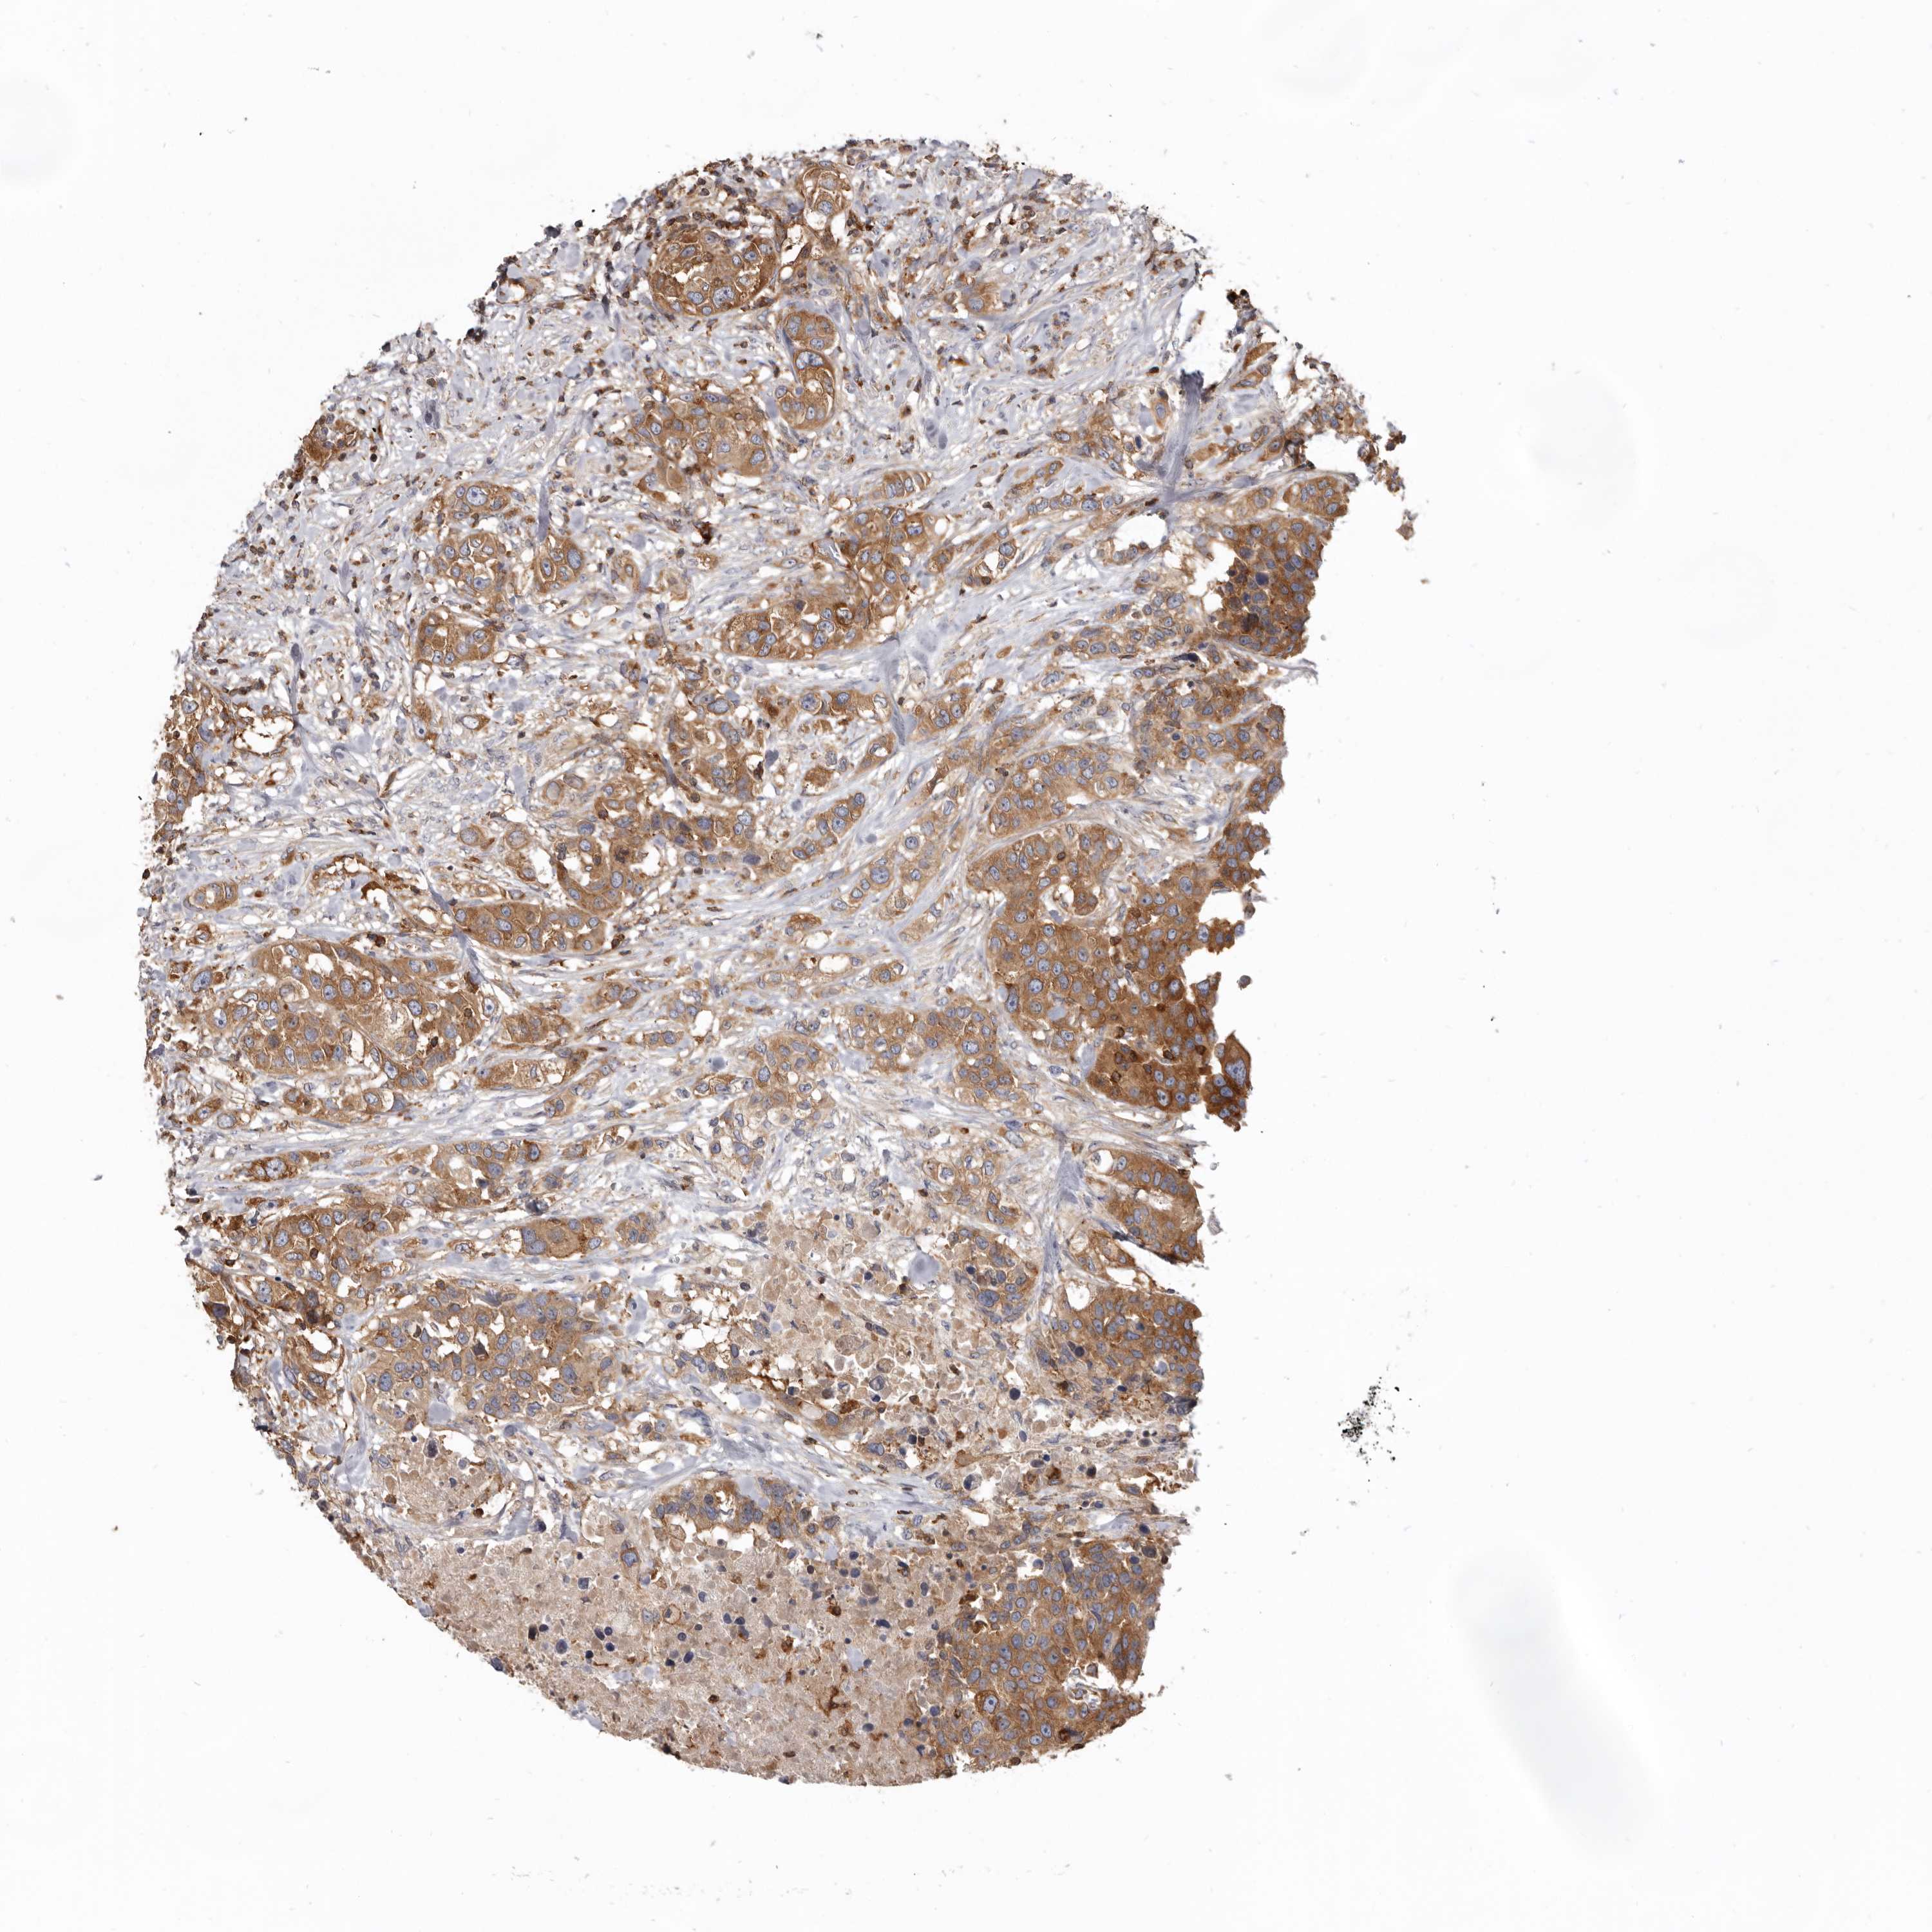

UROTHELIAL CANCER - Protein expressioni

A mouse-over function shows sample information and annotation data. Click on an image to view it in a full screen mode. Samples can be filtered based on level of antibody staining by selecting one or several of the following categories: high, medium, low and not detected. The assay and annotation is described here.

Note that samples used for immunohistochemistry by the Human Protein Atlas do not correspond to samples in the TCGA dataset.

Antibody stainingi

Antibody staining in the annotated cell types in the current human tissue is reported as not detected, low, medium, or high, based on conventional immunohistochemistry profiling in selected tissues. This score is based on the combination of the staining intensity and fraction of stained cells.

Each image is clickable and will lead to virtual microscopy that enables deeper exploration of all samples and also displays staining intensity scores, fraction scores and subcellular localization as well as patient and tissue information for each sample.

Antibody HPA027956

Antibody CAB004350

Urothelial carcinoma, Low grade

Urothelial carcinoma, High grade